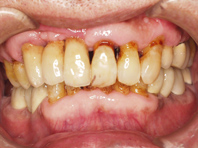

6ヶ月後、歯ぐきを開いて膜を取り除くと、骨がなかった所にしっかりと骨が作られ、インプラントが完全におおわれている状態が判ります。

完成写真